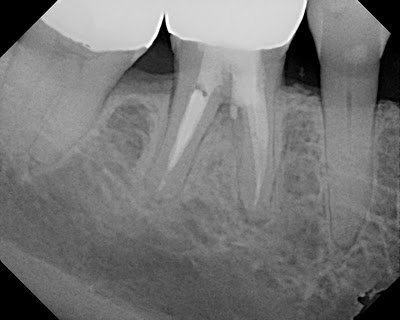

At 18 months, the lesion continues to improve, tooth is completely asymptomatic and functional. Proper endodontic treatment and repair with MTA has retained a tooth that many would have considered “hopeless” or non-restorable based on the amount of furcal bone loss.